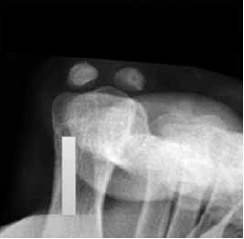

A seguir, observe a imagem de uma radiografia.

(Arquivo pessoal; imagem usada com autorização)

Assinale a alternativa que corretamente descreve o que está identificado na radiografia.